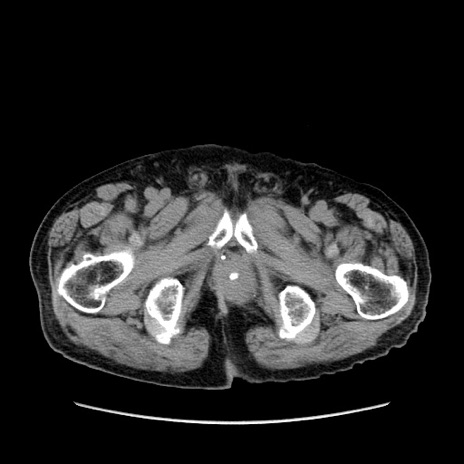

症例24(横断像)

【症例】80歳代男性

【主訴】左側腹部痛、嘔吐

【現病歴】本日早朝より左腹部に痛みあり。昼頃嘔吐認めたため、救急要請。

【既往歴】直腸癌(Mile手術)、胆摘

【身体所見】意識清明、BT 35.9℃、BP 221/93mmHg、SpO2 97%(RA) 、腹部:左ストーマ周囲に限局性の腹部膨隆あり。 膨隆部自発痛・圧痛あり・軟。

【データ】WBC 7700、CRP 0.09